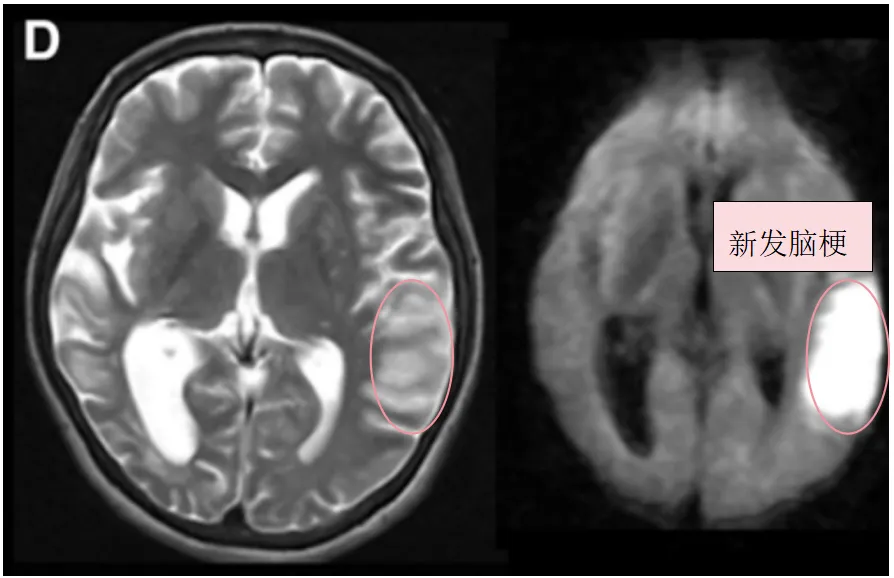

▼图1:A,术前血管造影(双侧颈总动脉正位图)显示双侧颈内动脉末端有“烟雾血管狭窄征象”,双侧大脑中动脉(MCA)狭窄(左)。术前Xe-CT显示双侧MCA区域脑血流减少(右:15.9,左:22.8 ml/100 g/min)(右)。

▼B,术前T2、DWI序列显示入院前1个月显示,既往右侧额顶叶脑梗死。